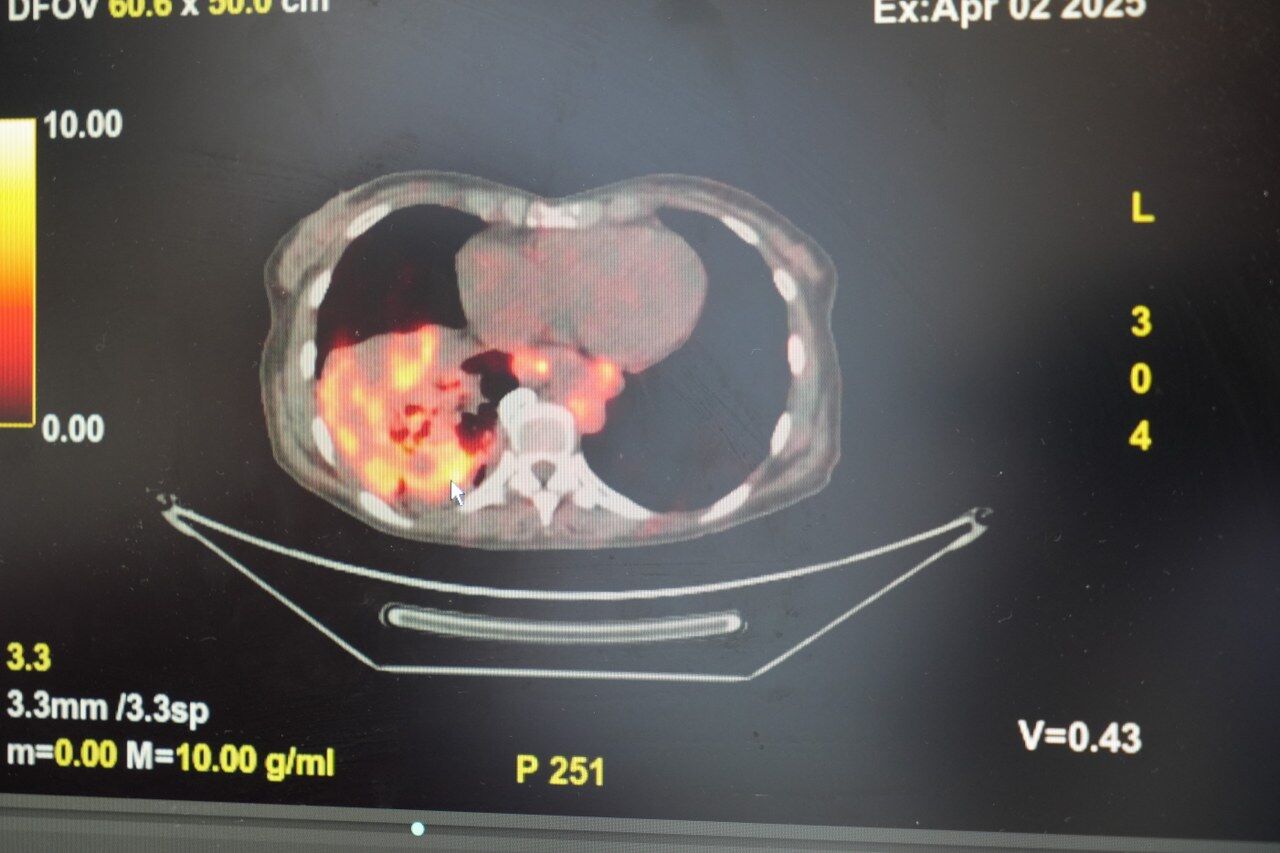

Dünyanın en prestijli tıp dergilerinden yayımlanan bir araştırma üzerinde açıklama yapan Prof. Dr. Şevket Özkaya, araştırmaya göre, sigara içmeyenlerde en sık görülen tür olan akciğer adenokarsinomu, kadınlarda akciğer kanserlerinin yaklaşık yüzde 60’ını oluşturduğunu söyledi. Prof. Dr. Özkaya, sigara dışındaki risk faktörlerinin başında radon gazının geldiğine dikkat çekerek, "Radon gazı, evlerimizde farkında olmadan soluduğumuz, renksiz, kokusuz, tatsız ve radyoaktif bir gazdır. Müsaade edilen değerlerin üzerinde solunduğunda akciğer kanseri riskini artırıyor. Radon gazı özellikle taş, toprak ve çimento gibi yapı malzemelerinde doğal olarak bulunuyor. Bu maddelerden ortama sürekli yayılan gaz, solunum yoluyla akciğerlere ulaşıyor" ifadelerini kullandı.